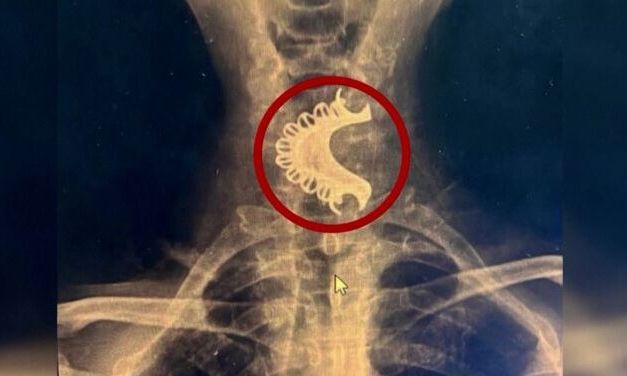

Σύμφωνα με τον χειρουργό Raul Maurtua, ο ηλικιωμένος άνδρας υπέφερε από έντονο πόνο και αναπνευστικά προβλήματα για τέσσερις ημέρες πριν αποφασίσει να αναζητήσει ιατρική βοήθεια. Αρχικά, πίστευε πως η οδοντοστοιχία είχε αποβληθεί μετά το επεισόδιο, αγνοώντας ότι είχε παραμείνει σφηνωμένη στο λαιμό του.

Η πρώτη διάγνωση έγινε στο τοπικό νοσοκομείο του Huacho, όπου οι γιατροί έκαναν ακτινογραφία και εντόπισαν την οδοντοστοιχία. Ωστόσο, λόγω της κατάστασης της, αποφασίστηκε η μεταφορά του στο νοσοκομείο Sabogal στο Λίμα για πιο σοβαρή φροντίδα. Εκεί, μια ιατρική ομάδα πραγματοποίησε την επέμβαση, αφαιρώντας την οδοντοστοιχία με επιτυχία.